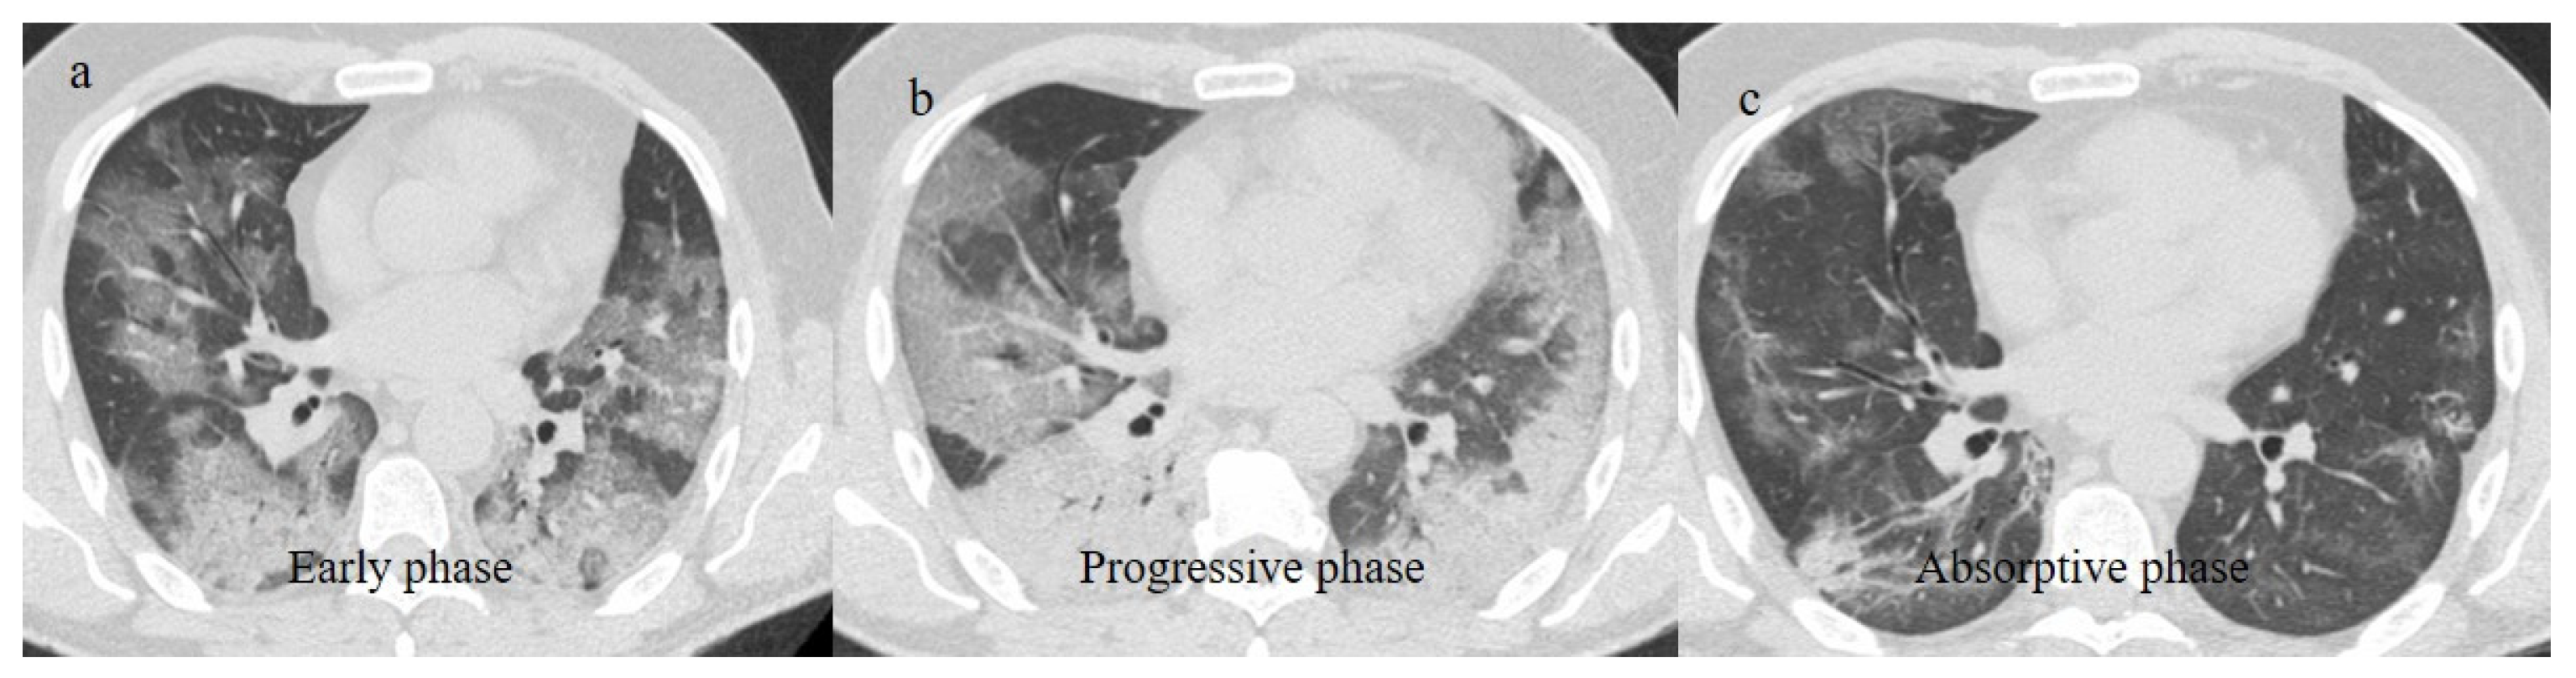

An uncontrolled immune response to SARS-CoV-2 infection can lead to acute respiratory distress syndrome (ARDS), which was a relatively common complication of COVID-19 pneumonia in the first waves [99,100,101,102,103,104]. COVID-19 patients with ARDS were usually older and had comorbidities [100]. The majority of patients with ARDS required mechanical ventilation and were prone to complications including barotrauma with alveolar rupture and superimposed bacterial pneumonia [101,102,103].

COVID-19 ARDS is caused by both direct viral action and the indirect effect of the hyperactivation of the host immune system, which can cause the excessive production of proinflammatory cytokines, i.e., cytokine storms. COVID-19 ARDS differs from typical ARDS due to the existence of endothelial injury characterized by the presence of pulmonary capillary microthrombi, in addition to typical diffused alveolar injury [99,100,101,102,103,104,105]. This was revealed by histopathological examinations, although autopsies were rare in the first wave of the pandemic [103]. SARS-CoV-2 mainly attacks the endothelium through the ACE2 receptor. The injured pulmonary endothelium loses lung perfusion regulation with the activation of an intrapulmonary shunt. Thus, the lung volume and lung compliance are almost normal [99,100,101,102,103,104,105]. Therefore, COVID-19 ARDS is characterized by silent or happy hypoxemia. The imaging features of COVID-19 ARDS were similar to those of ARDS with other etiologies [103]. Chest CT findings were characterized by the anteroposterior gradient of the lung opacities. The rapid progression of lung opacities involving all five lobes in a patient with COVID-19 should also increase concern for ARDS. In the acute phase, a tendency towards dense consolidation involving the dependent posterior lower lobes while mostly sparing the anterior or non-dependent area has been observed [37,103] (Figure 15).

Figure 15.

Chest CT scan of a 51-year-old patient during the Alpha variant period (February 2021) showing in image (a) posterior consolidations with diffuse GGOs compatible as ARDS on the axial plane and in image (b) on the coronal plane.

ARDS in COVID-19 patients has been frequent since the Delta variant [37,99,104,105,106]. However, the risk of ARDS was lower during the Omicron variant [107]. Some rare cases of ARDS were reported after COVID-19 vaccinations as possible consequences of antibody-dependent enhancement (ADE) [108,109] (Figure 16).

Figure 16.

Chest CT scan of a 70-year-old patient during the Alpha variant period (April 2021) with ARDS findings in the superior lobes as shown in image (a) and inferior lobes in image (b). The patient developed severe COVID-19 pneumonia, which evolved into ARDS a few days after the COVID-19 vaccination.